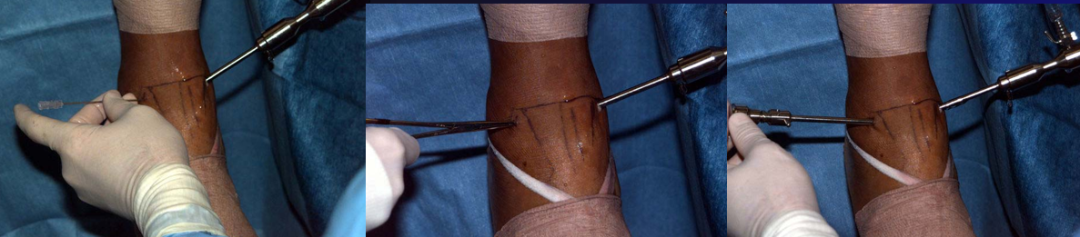

关节镜辅助下踝关节融合术

孔德春 男性 52岁

术后

植入异体骨条

关节清理后不植骨